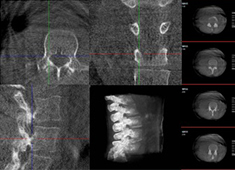

机器人做胸椎手术怎么样:经皮钉棒系统内固定术案例分享使用骨科手术机器人做胸椎手术的效果怎么样?今天普爱医疗分享一则临床案例——经皮钉棒系统内固定术,看看普爱手术机器人如何助力手术顺利进行。... 发布时间:2024-08-29 11:42:06

术中三维CT如何辅助手术机器人完成手术导航手术机器人对术中配准的要求较高,仅依靠其自身的导航定位功能还远远不够,需要结合术中三维CT影像来提高导航精准度。术中三维CT是如何辅助手术机器人完成手术导航的?下面以术中三维移动C臂(PLX C7600)辅助脊柱外科手术... 发布时间:2024-08-06 16:57:10